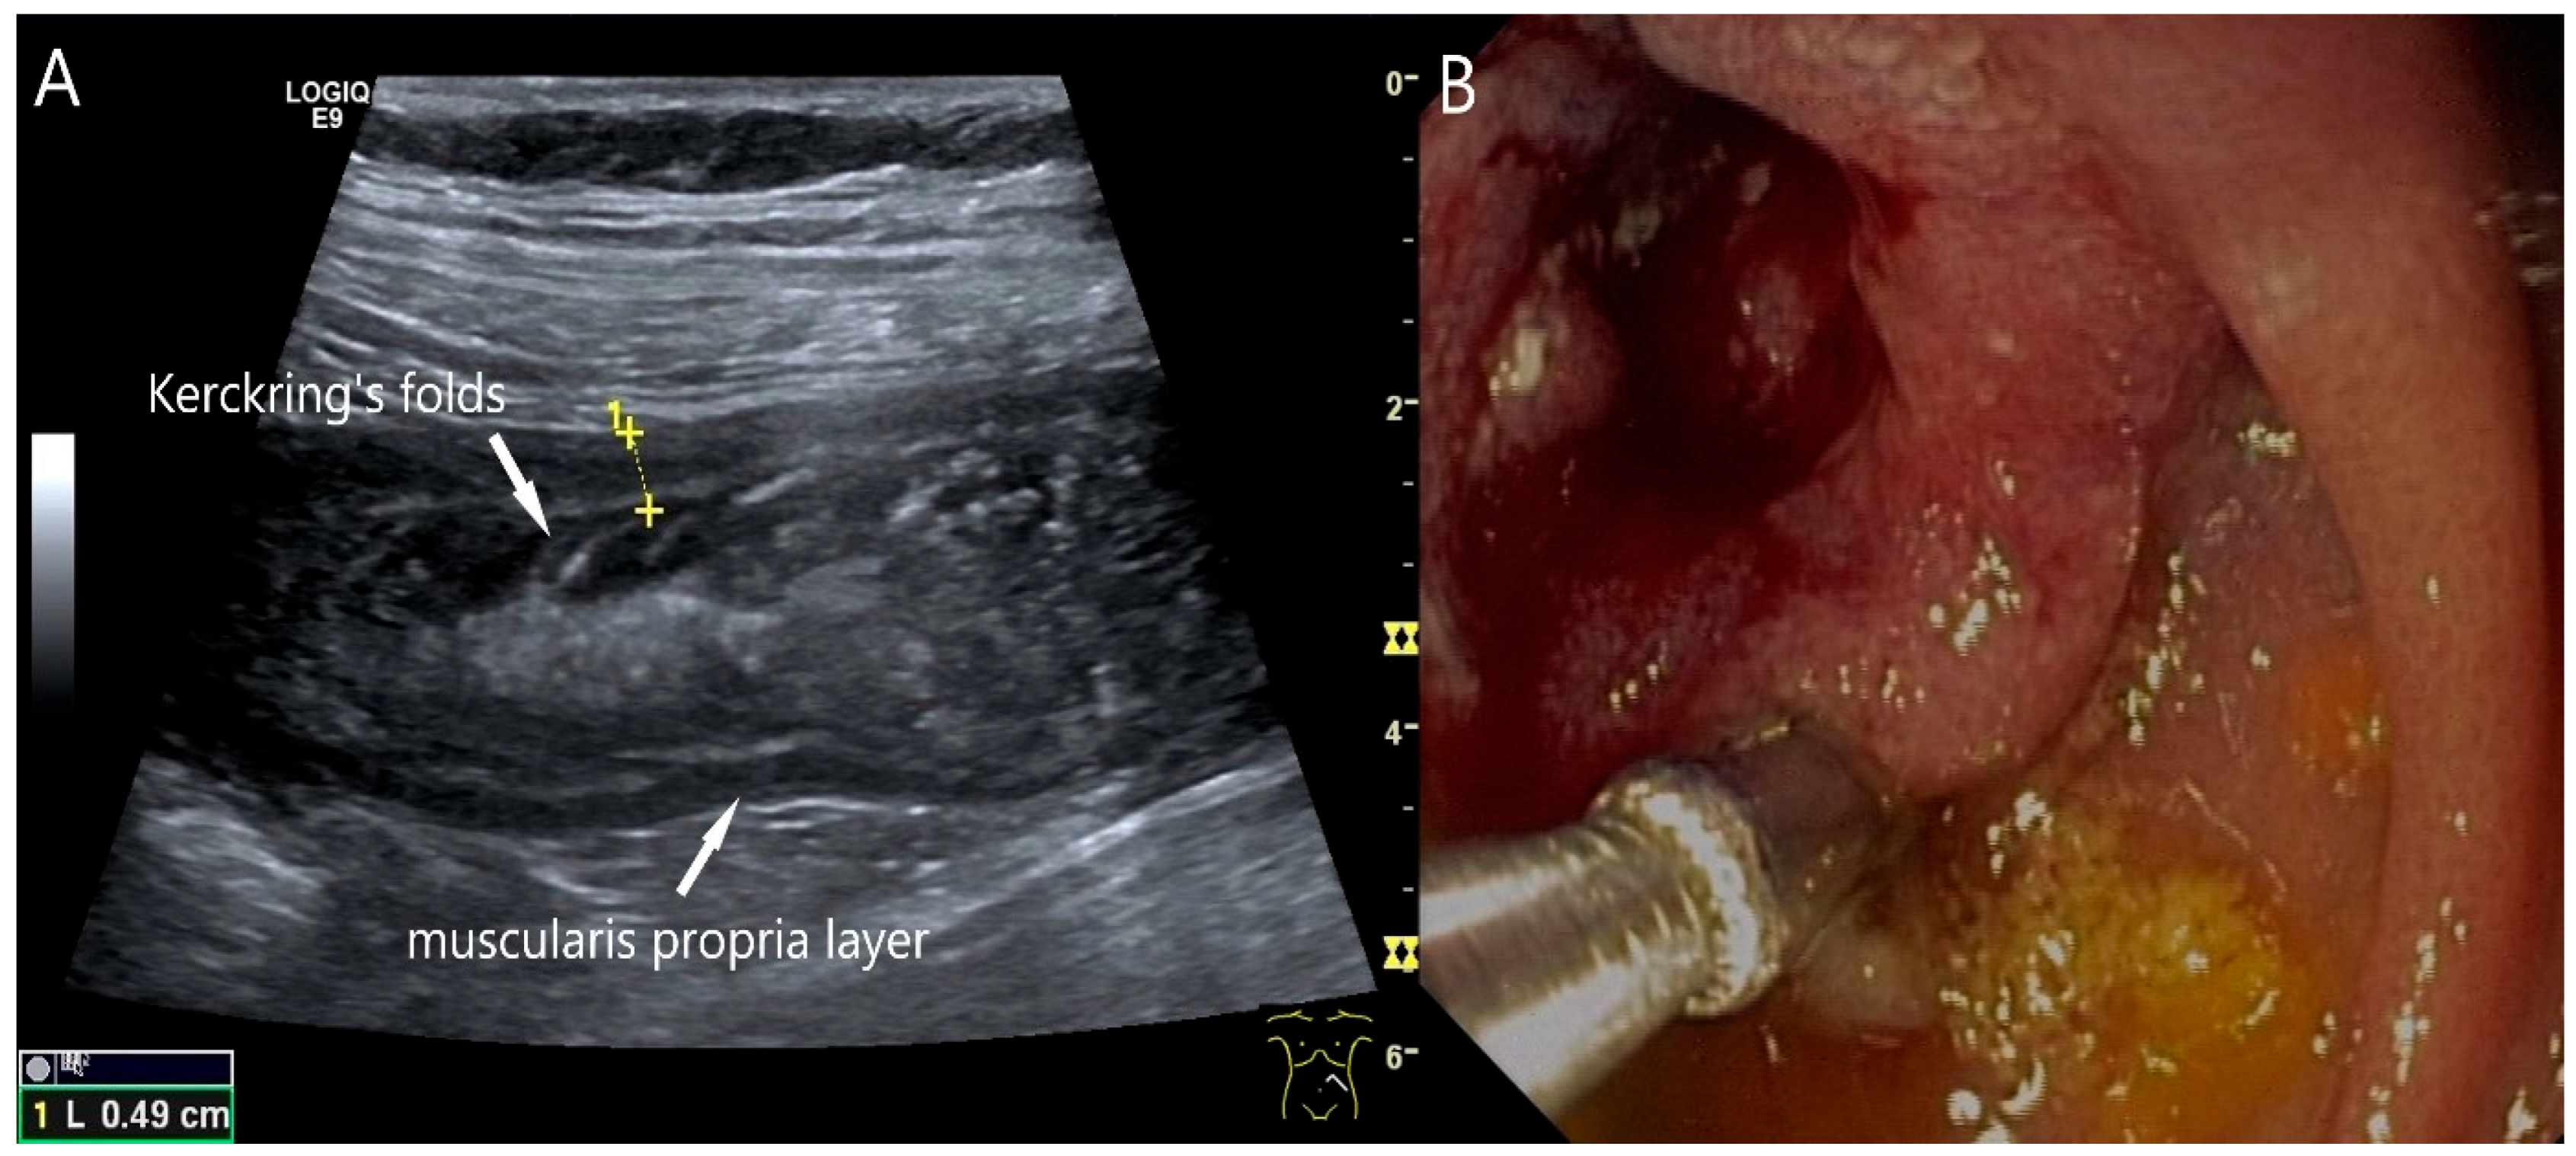

- Wu, S.; Yu, H.; Liu, Y.; Zhou, H.; Zhou, Y. Small bowel adenocarcinoma of the jejunum detected by double contrast enhanced ultrasound: A case report of a novel ultrasound modality. Front. Oncol. 2024, 14, 1288041. [Google Scholar] [CrossRef]

| Neuroendocrine tumor | Small, nodular hypoechoic wall thickenings, mostly in the submucosa with spreading into the other layers. Usually with small vessels on CDI. Regionally enlarged lymph nodes. Multilocular manifestations are possible. |